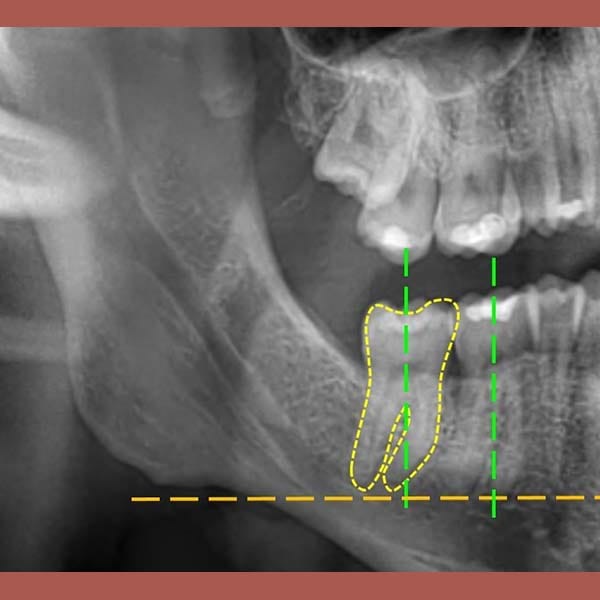

حالة رحى سفلية منطمرة و مائلة في الطرف الأيمن تم تعديلها تقويمياً و رحى سفلية مائلة في الطرف الأيسر أيضاً تم تعديلها تقويمياً